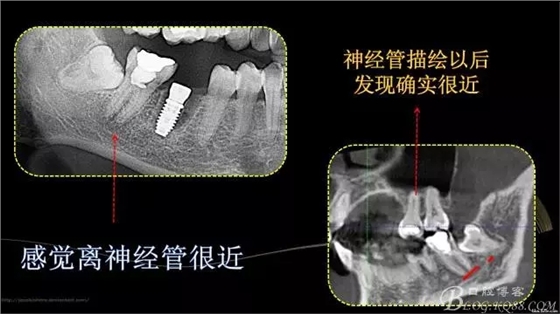

行走在神經(jīng)管上的根管治療